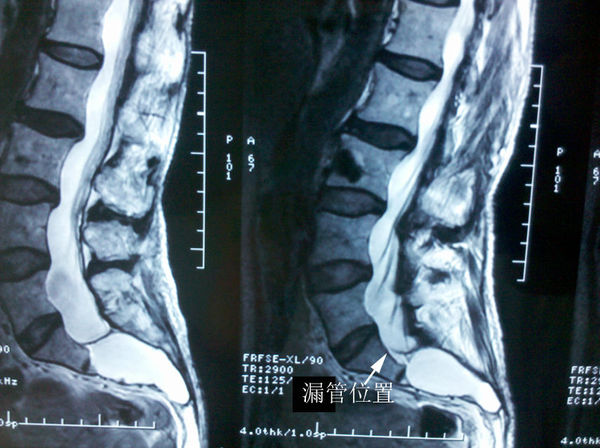

前磁共振上可见,囊肿从骶1下段一直延伸到骶5,严重侵袭了骶骨。骶尾神经根损害很严重,大小便障碍已经非常严重。还有明显的骶尾会阴部疼痛。磁共振上显示了漏管的位置。如果不封堵漏管,这么巨大的骶管囊肿是无法治愈的。